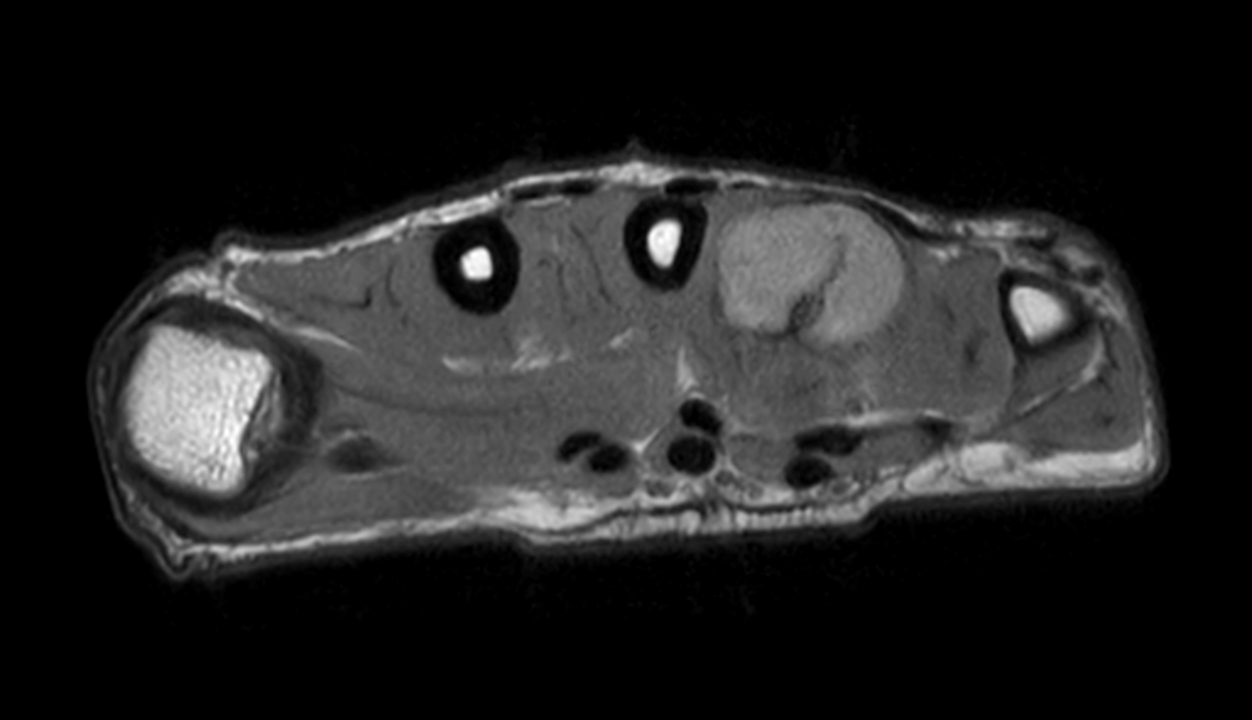

Axial PDw mDIXON XD TSE (Water only)

Axial PDw mDIXON XD TSE (In Phase)

Axial PDw mDIXON XD TSE (Partial FatSat)